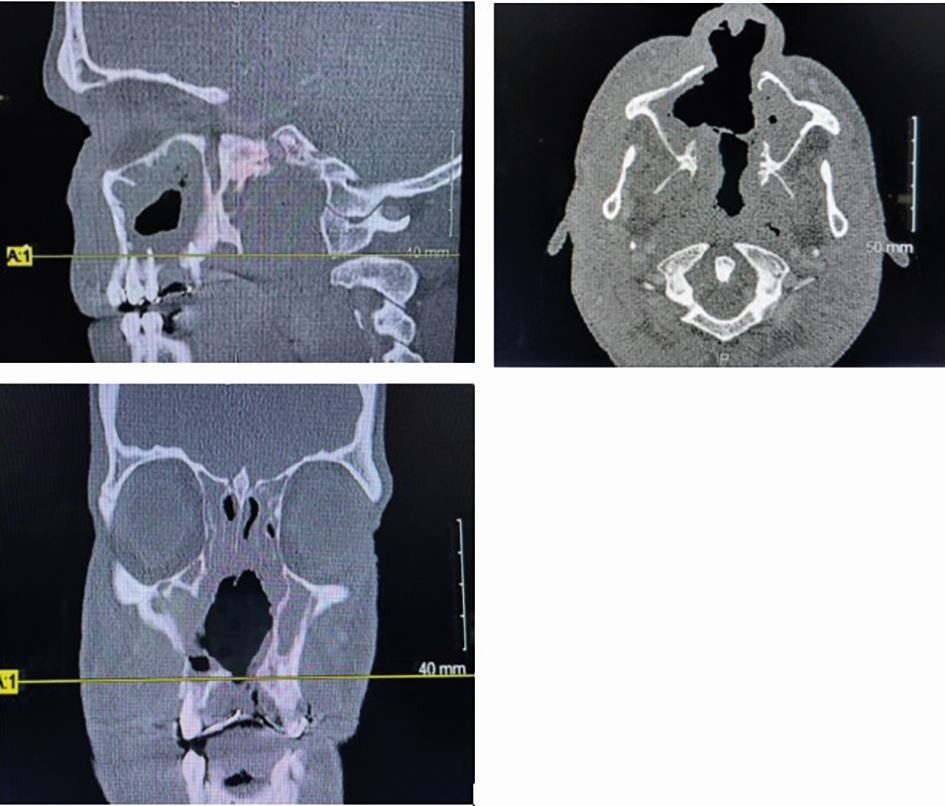

Head and neck CT for Case 2, highlighting the extent of the CIMDL